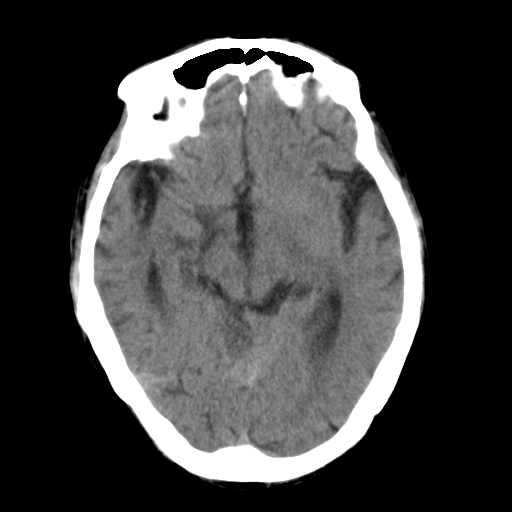

标题: CT25306:男性,75岁。右侧肢体无力一周。 [打印本页]

标题: CT25306:男性,75岁。右侧肢体无力一周。

右侧小脑楔形片状低密度影,考虑脑梗塞,建议mri或增强检查除外肿瘤占位

1)右侧小脑梗塞。2)脑萎缩。